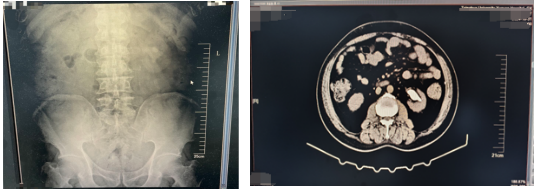

术后带输尿管支架管1个月左右对比图:

由CT可见:患者左侧肾盂输尿管支架术后改变,较术前左肾结石体积基本消失,原左侧输尿管上段结石、左肾盂-输尿管结合部扩张较前未见。